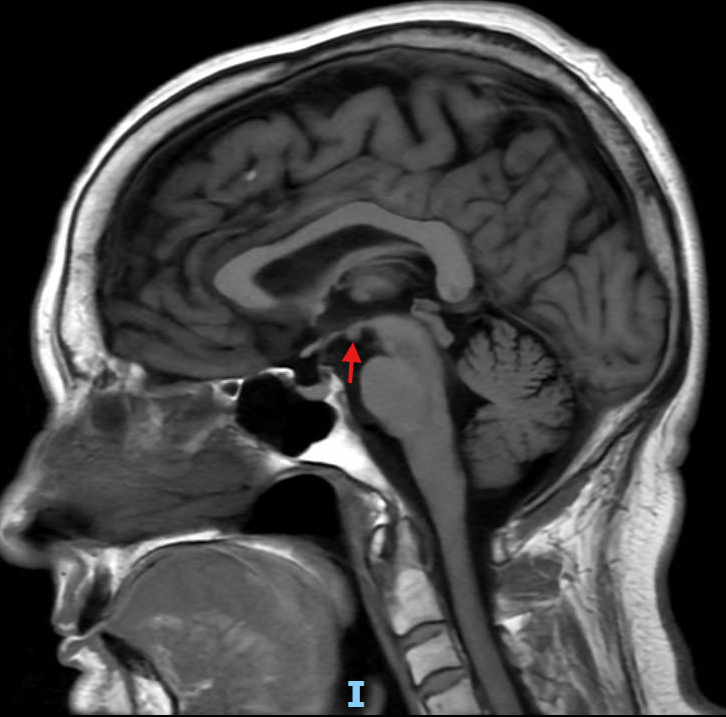

All models agree the image points to the mammillary body, with the key interpretation being Wernicke encephalopathy from alcohol-related thiamine deficiency; there is no notable disagreement beyond minor wording differences about the clinical triad and MRI appearance.